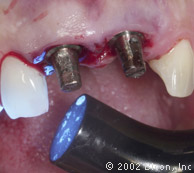

Установка двух 5.0mm x 8.0mm HA имплантантов Bicon

Определение направления оси и глубины шахты имплантантов

Вид после установки